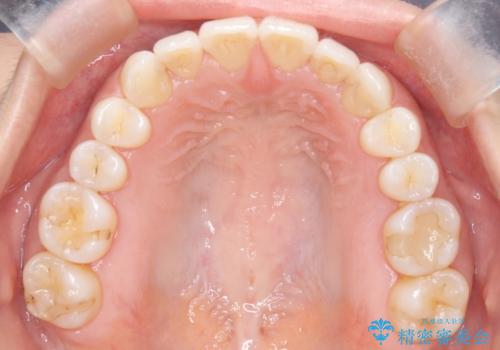

【インビザライン】前歯のねじれを治したい

- 前歯のガタガタを主訴に来院されました。

叢生の量は軽度でしたが臼歯の遠心移動を行い、インビザラインにて治療をしました。

叢生の改善に必要なスペースは遠心移動やIPRで作ることが可能です。今回は遠心移動をメインにスペースを作って叢生の改善を行いました。